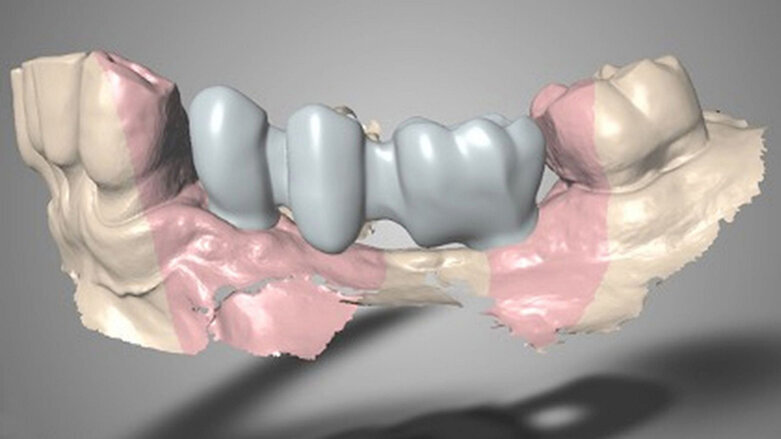

V místech zubů 34 a 36 byla naplánována fixní náhrada nesená implantáty. Z tohoto důvodu bylo provedeno vyšetření pomocí CBCT, které mělo pomoci posoudit kvalitu a kvantitu kosti pro zavedení implantátu (obr. 4, 5). Byl shledán dostatek vertikální kosti v obou místech, nicméně v oblasti zubu 34 bylo pro zavedení implantátu nedostatečné horizontální množství kosti. V této lokalitě byla tedy spolu se zavedením implantátu naplánována augmentace kosti pomocí xenoštěpu a kolagenní membrány a keramický vhojovací abutment.